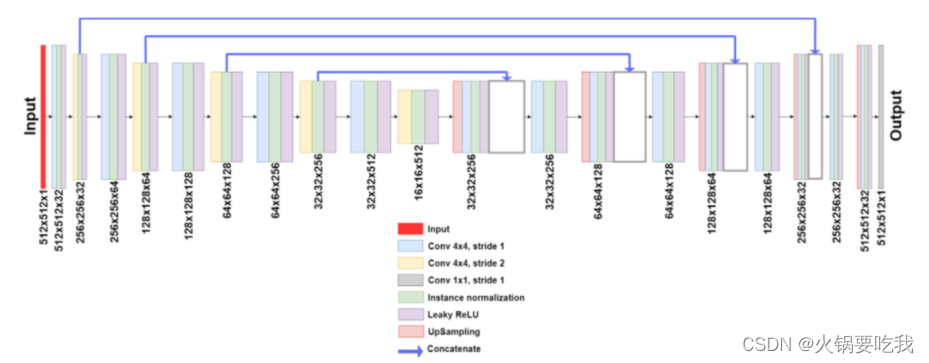

生成器:典型的UNet结构